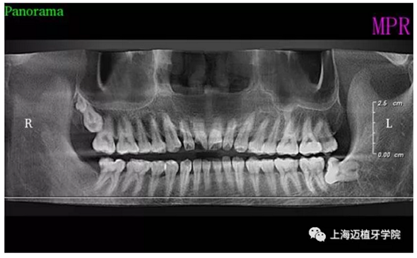

術(shù)前全景片

主訴:前門外傷牙根折要求修復?現(xiàn)病史:前門牙外傷,劈裂至根部,無法固定及其他修復,要求種植?檢查:11牙冠2/3缺損,唇腭向劈裂,唇部紅腫。 CT示根折, 骨寬度9.47mm,距鼻底12.34mm,Ⅲ類骨。 口腔衛(wèi)生一般